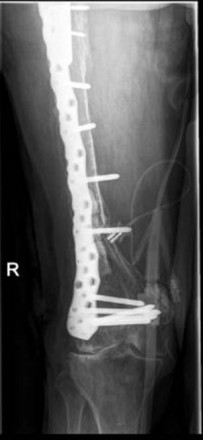

89 year old female patient with a Vancouver C Type fracture; OTA fracture pattern 32 A 2.

Overall 3 periprothetic fractures after THR 1998

1. 2001 distal fracture treated with dynamic condylar screw and PMMA cement

2. 2011 a Vancouver B1 fracture has been treated with removal of distal plate and proximal angle stable plating with cerclage wires.

3. 2013 The old implant has been removed and the fracture bridged with a long NCB distal Femur plate. A sufficent overlap of the hip stem could be achived with bicortical screw fixation around the stem